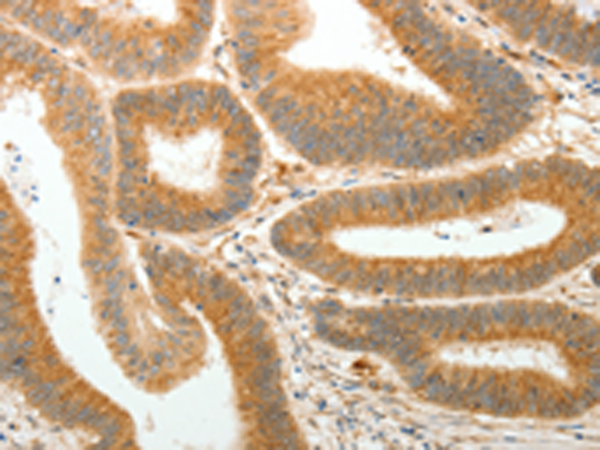

分类: 科研抗体货号: P11181别名: AMD; SAMDC; ADOMETDC应用: IHC反应种属: Human, Mouse, Rat